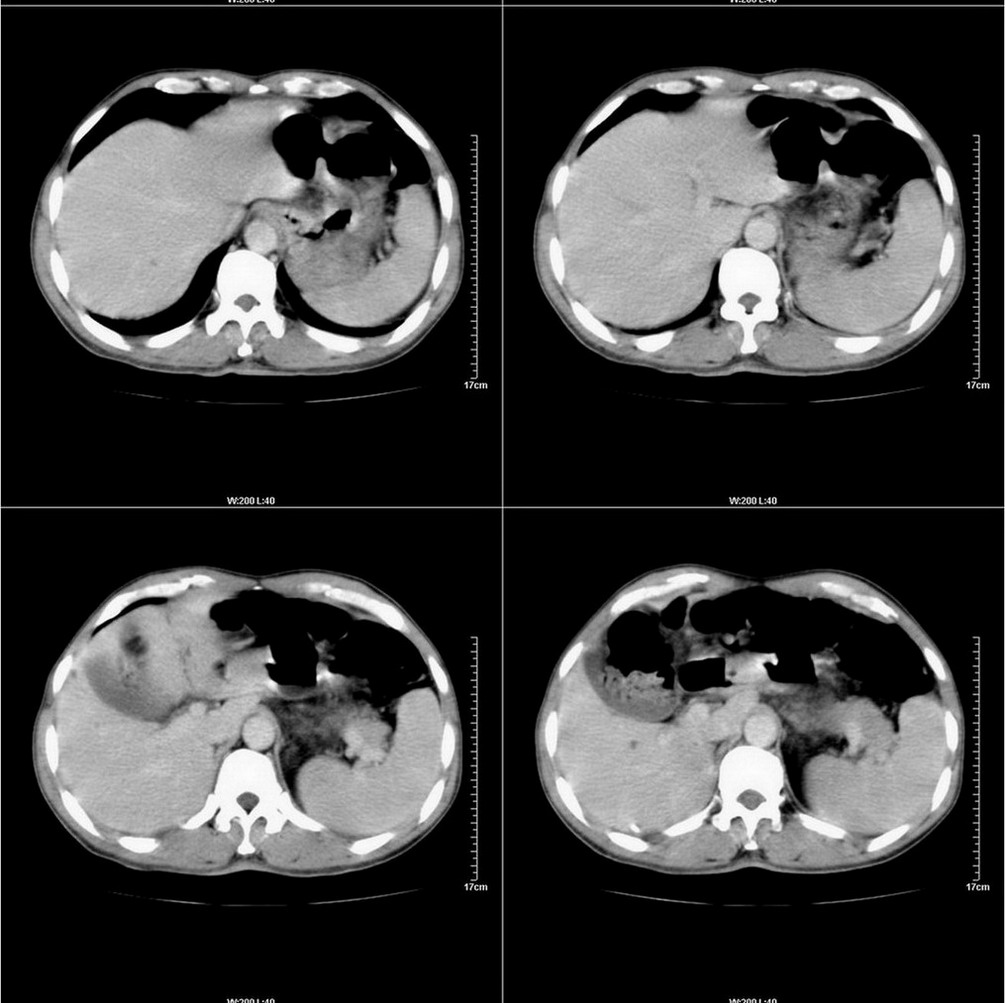

标题: CT14220:男性,59岁。腹部疼痛不适半年余。 [打印本页]

标题: CT14220:男性,59岁。腹部疼痛不适半年余。

胃壁弥漫增后,考虑胃炎溃疡

建议结合胃镜或钡餐检查,考虑胃底贲门癌可能性大。

考虑:1、肝右叶下部小囊肿;

2、胃可能为准备充盈不良所致,必要时请胃镜进一步检查。